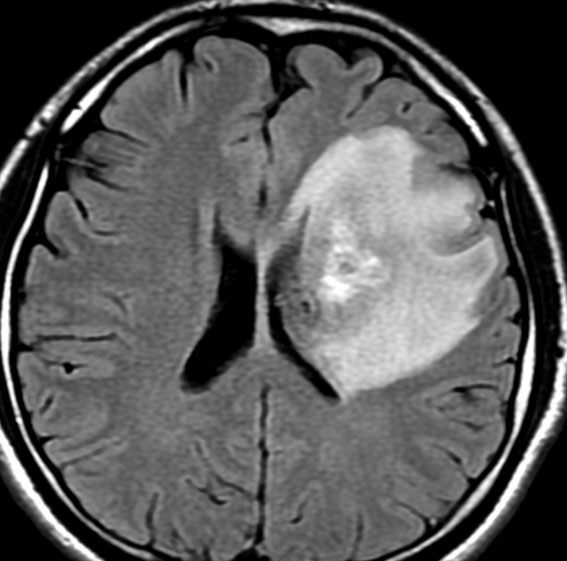

pseudoprogression スード・プログレッション

放射線治療の4ヶ月後くらいから腫瘍が大きくなりはじめ,麻痺が悪化しました。画像は放射線治療9ヶ月後のものです。腫瘍は大きくなって,周囲の脳浮腫が悪化して,閉塞性水頭症になっています。この間,大量のリンデロンを使いましたので,ステロイド治療の副作用で肥満になりました。この例のような,のう胞性拡大のようにみえるスードプログレッションは毛様細胞性星細胞腫の放射線治療後に特徴的に生じるものです。

この時点で再燃(再発)と間違って,あわてて危険な開頭手術をしてはなりません!

何にもしないで治ってしまう

我慢に我慢を重ねて,放射線治療後16ヶ月後です。腫瘍は消失しましたし,左片麻痺も良くなって,少年は野球ができるようになりました。